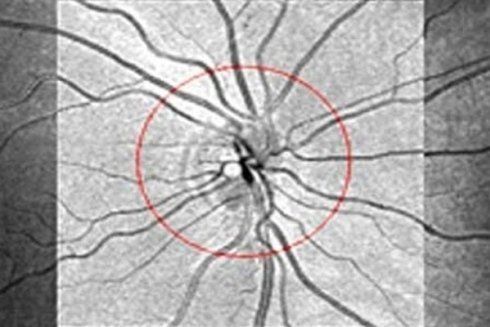

- Trattamento Laser Retina

- Trattamento Laser Glaucoma